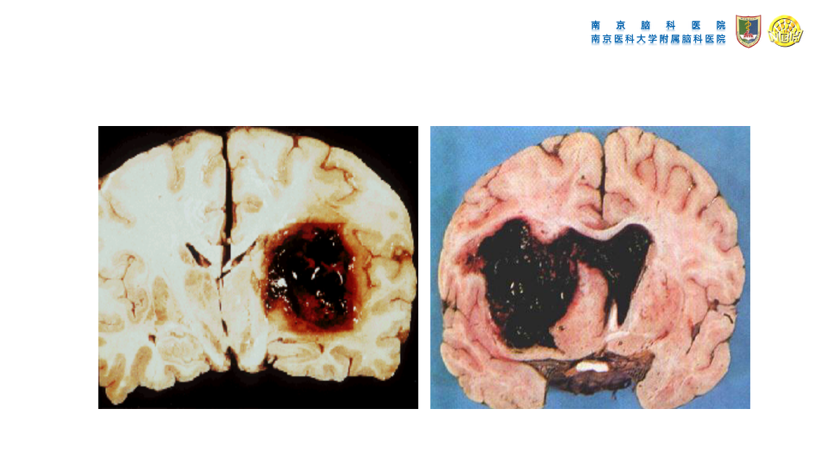

高血压性脑出血的微创手术治疗(高血压性脑出血的血压管理、镇静镇痛处理、手术指征、手术方法等重要问题)